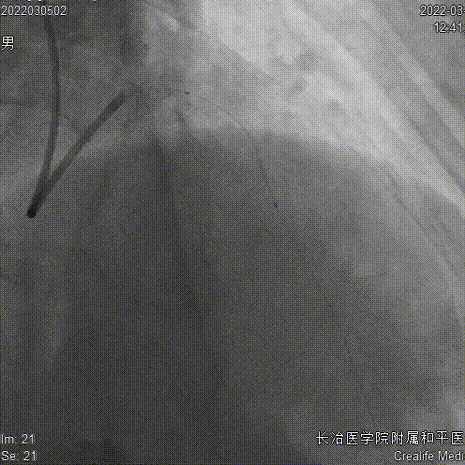

CAG

复查CAG